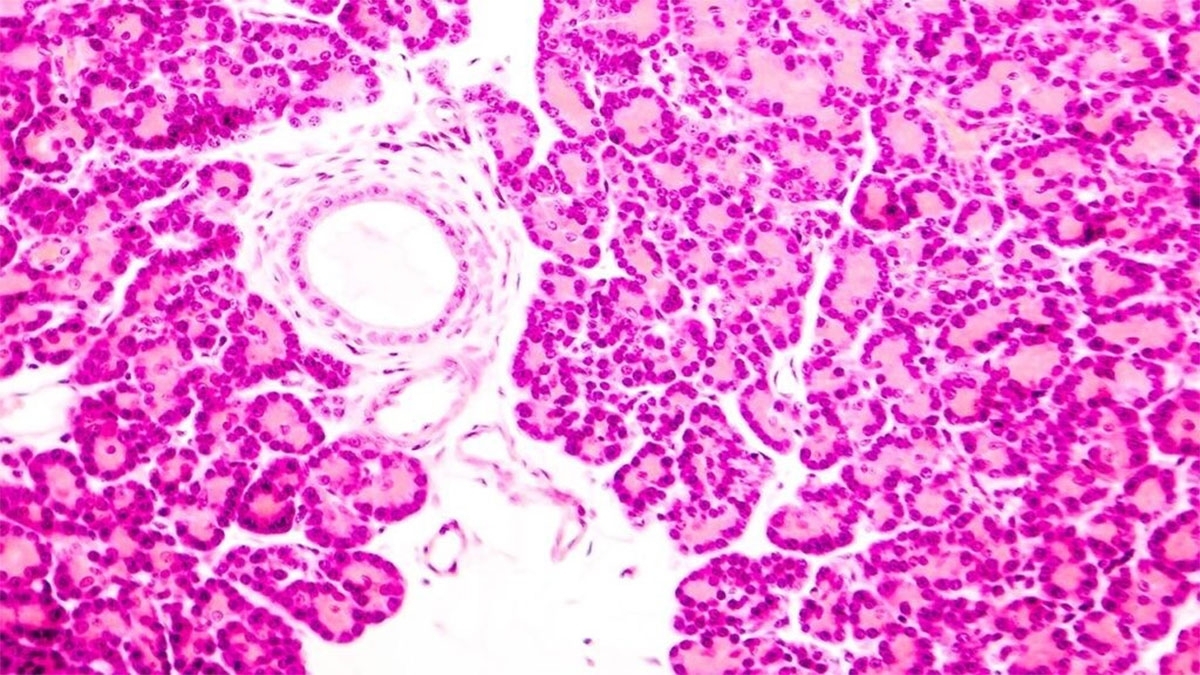

دیابت نوع ۱ زمانی رخ میدهد که سیستم ایمنی بدن دچار اختلال شده و به سلولهای ایزولهٔ بتا در لوزالمعده که تولیدکنندهٔ انسولین هستند، حمله میکند. اگرچه سلولهای ایزولهٔ سالم میتوانند از فرد دیگری پیوند زده شوند، اما احتمال حمله یا رد شدن آنها توسط بدن همچنان بالاست.

نتیجه این بود که سلولهای پیوندی مانند مهاجمان خارجی شناخته نشدند و سیستم ایمنی دوباره عملکرد طبیعی خود را آغاز کرد. هرچند بخشی کوچک از سلولهای ایزوله نشانههایی از التهاب داشتند، اما این بافت حیاتی مورد حمله قرار نگرفت.